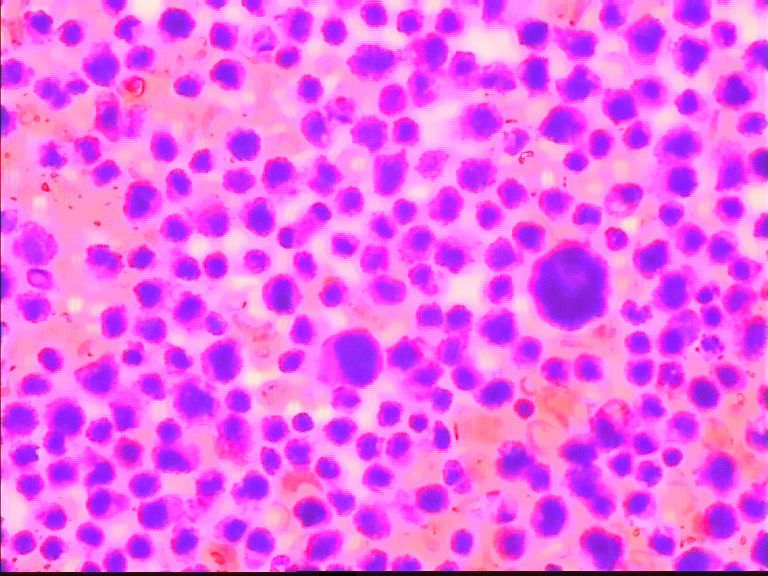

68岁,男,CT示胆囊有增粗影,余检查无殊,临床考虑胃肠道肿瘤。肿瘤指标均正常。

片子里面这种细胞很多,让我总是觉得有问题,但是又不敢报癌,拍的还是最典型的 感觉核好像看起来有点奇怪,也不知道是什么原因

这些图片应该是干性固定的吧,细胞退变明显;我刚看这些涂片的时候;如果不是楼主提示是胸水;我以为还是在看骨髓的HE涂片;请注意不要只注意哪些大细胞,还要仔细看那些背景中有核的细胞,大小不等;有异型性;请楼主提供病人的外周血象结果和其他相关临床情况;如果那些大细胞是巨核细胞,那这个病人很可能是白血病或淋巴造血肿瘤;另要注意鉴别其他未分化癌或肉瘤。

同样考虑恶性肿瘤,首选 淋巴造血系统疾病。期待继续!

个人倾向低分化腺癌。如果是淋巴造血系统的肿瘤,胞浆太多了些。

背景中的细胞也是有些大小不一,考虑淋巴造血系统的肿瘤,期待进一步的结果

免疫组化结果 最后为淋巴瘤